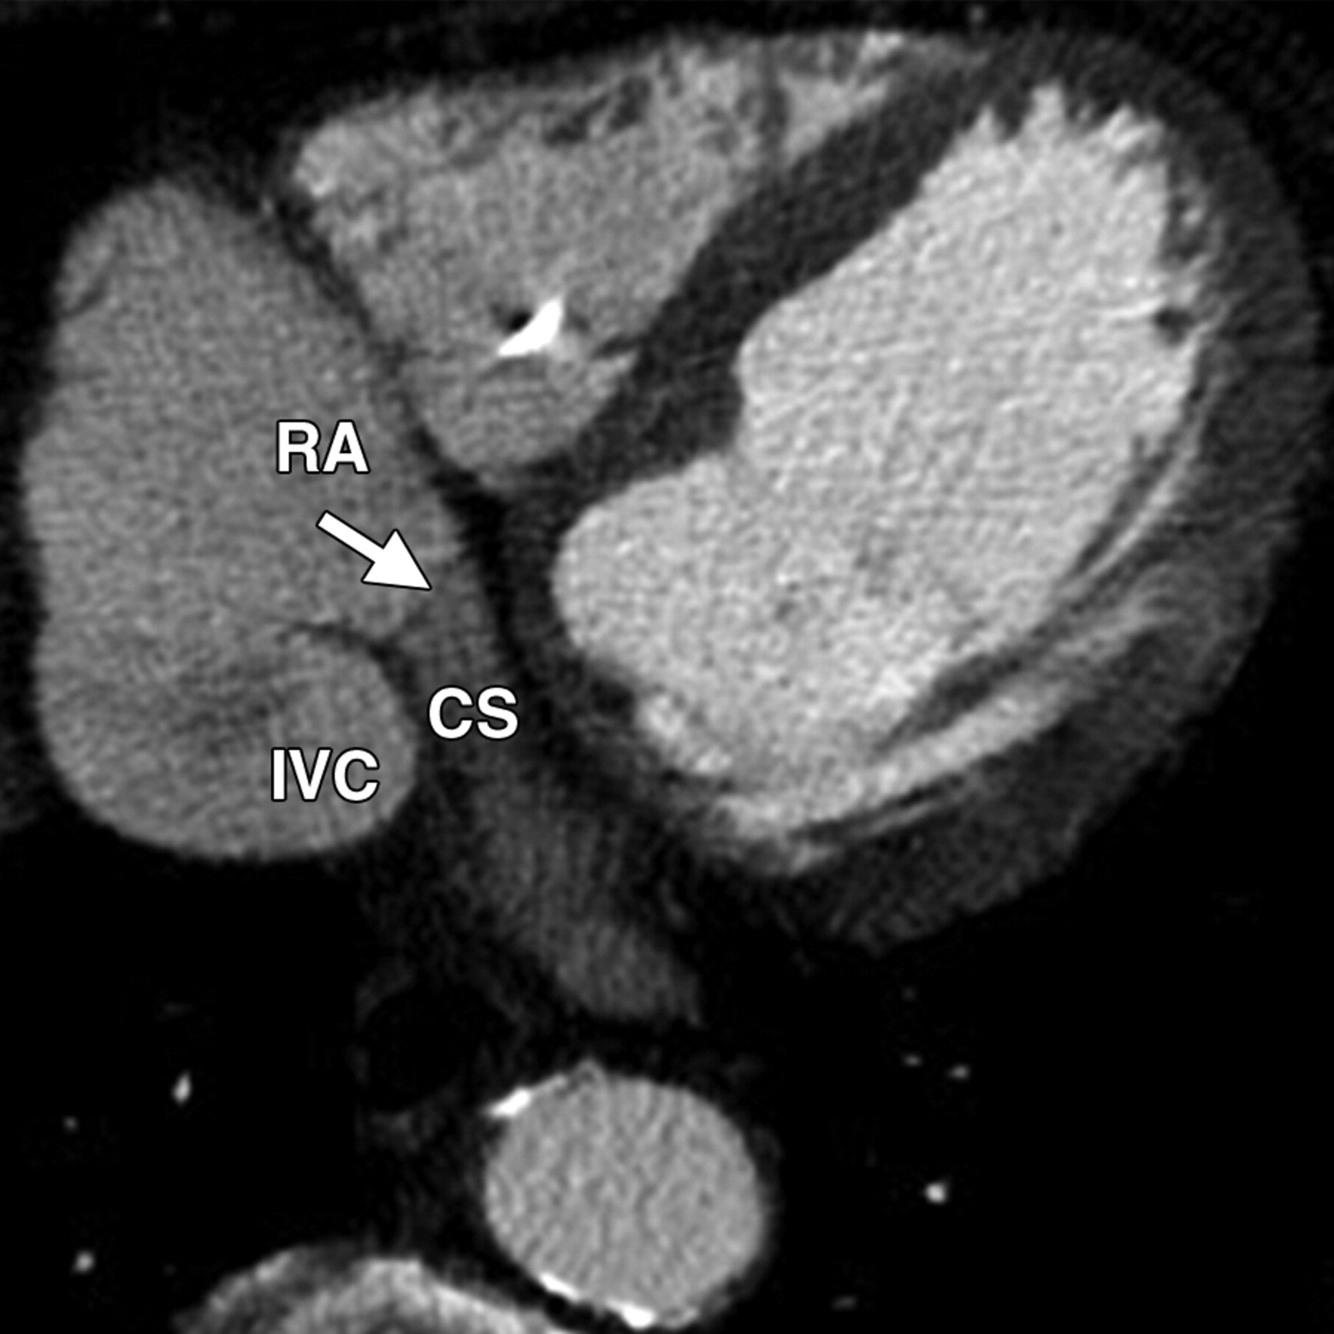

thebesian valve

(@ junction of coronary sinus and RA)